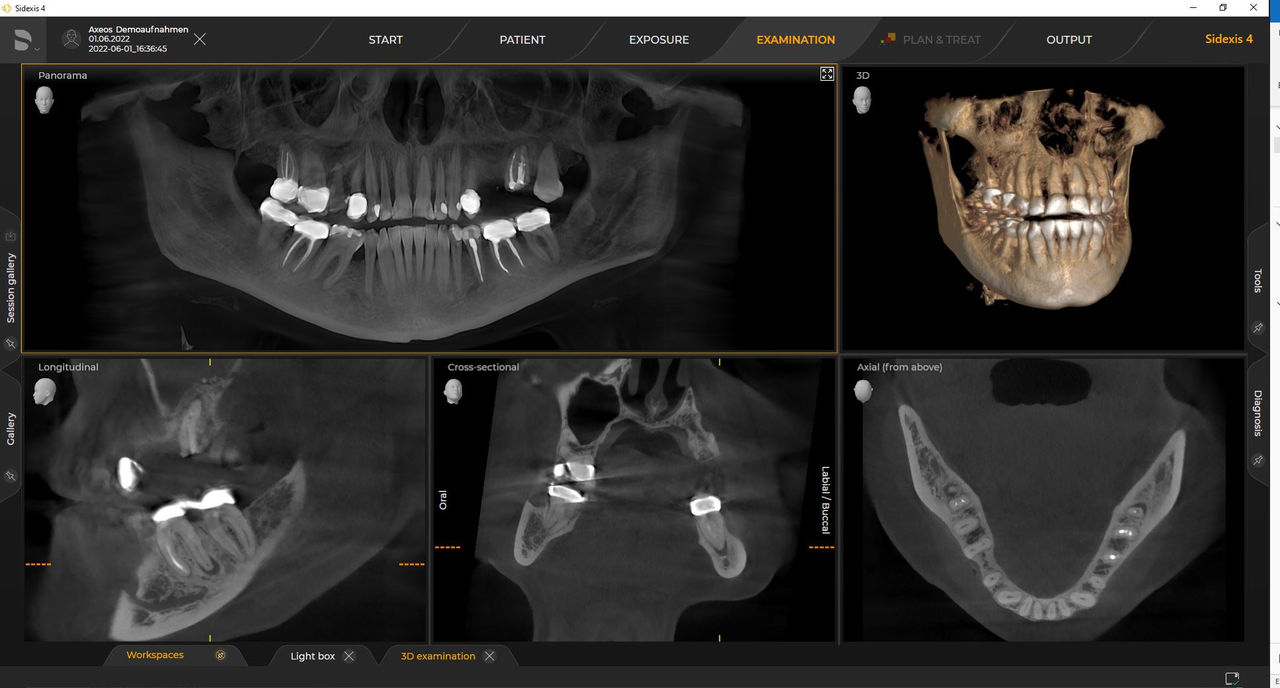

Axeos, el sistema especializado 2D/3D con un gran volumen y alta calidad de imagen para clínicas con una amplia oferta de tratamientos. Desarrollado junto a dentistas y clínicos, Axeos ofrece la gama más completa de funciones de todos los equipos de radiología extraoral de Dentsply Sirona. Además de una excelente calidad de imagen y tamaños de volumen 3D personalizados, el equipo de radiología dental está completamente optimizado para una mayor comodidad del paciente. Axeos no solo proporciona calidad en rendimiento y comodidad, sino también con su galardonado diseño gracias al gabinete integrado para el almacenamiento de posicionadores de mordida y la luz ambiental.

Las unidades 3D de Dentsply Sirona funcionan exclusivamente con Sidexis 4. Sin embargo, la migración de datos de Sidexis XG a Sidexis 4 es muy fácil. Sidexis 4 permite una experiencia digital completa con las últimas herramientas.